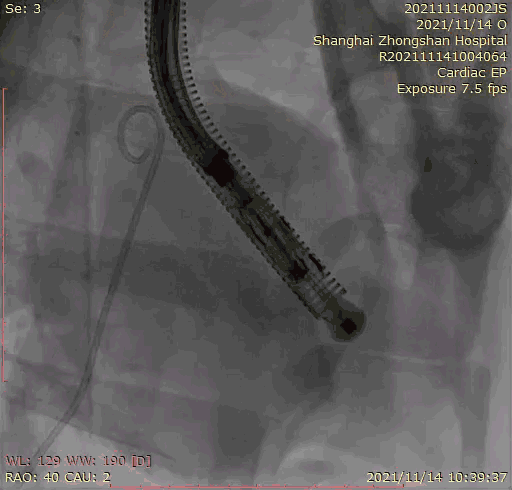

本次臨床前研究經右側頸靜脈置入LuX-Valve Plus輸送系統(tǒng)可調彎鞘管,在DSA及超聲引導下將人工三尖瓣瓣膜植入到原有三尖瓣位置,利用獨特的錨定技術將人工瓣膜支架可靠固定在預定的位置。

上海中山醫(yī)院葛均波院士、錢菊英院長、周達新教授、潘文志教授、潘翠珍教授、李偉教授共同完成此次臨床前研究。術后葛均波院士對Lux-Valve Plus的器械操作性能給予了高度評價,DSA和超聲影像也顯示出在本次研究中Lux-Valve Plus的安全性和有效性俱佳。